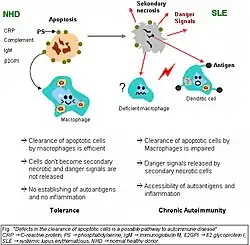

Clearance deficiency

Impaired clearance of dying cells is a potential pathway for the development of this systemic autoimmune disease. This includes deficient phagocytic activity, impaired lysosomal degradation, and scant serum components in addition to increased apoptosis.[90]

SLE is associated with defects in apoptotic clearance, and the damaging effects caused by apoptotic debris. Early apoptotic cells express "eat-me" signals, of cell-surface proteins such as phosphatidylserine, that prompt immune cells to engulf them. Apoptotic cells also express find-me signals to attract macrophages and dendritic cells. When apoptotic material is not removed correctly by phagocytes, they are captured instead by antigen-presenting cells, which leads to the development of antinuclear antibodies.[6]

Monocytes isolated from whole blood of people with SLE show reduced expression of CD44 surface molecules involved in the uptake of apoptotic cells. Most of the monocytes and tingible body macrophages (TBMs), which are found in the germinal centres of lymph nodes, even show a definitely different morphology; they are smaller or scarce and die earlier. Serum components like complement factors, CRP, and some glycoproteins are, furthermore, decisively important for an efficiently operating phagocytosis. With SLE, these components are often missing, diminished, or inefficient.[90]

Macrophages during SLE fail to mature their lysosomes and as a result have impaired degradation of internalized apoptotic debris, which results in chronic activation of Toll-like receptors and permeabilization of the phagolysosomal membrane, allowing activation of cytosolic sensors. In addition, intact apoptotic debris recycles back to the cell membrane and accumulate on the surface of the cell.[91][92]

Recent research has found an association between certain people with lupus (especially those with lupus nephritis) and an impairment in degrading neutrophil extracellular traps (NETs). These were due to DNAse1 inhibiting factors, or NET protecting factors in people's serum, rather than abnormalities in the DNAse1 itself.[93] DNAse1 mutations in lupus have so far only been found in some Japanese cohorts.[94]

The clearance of early apoptotic cells is an important function in multicellular organisms. It leads to a progression of the apoptosis process and finally to secondary necrosis of the cells if this ability is disturbed. Necrotic cells release nuclear fragments as potential autoantigens, as well as internal danger signals, inducing maturation of dendritic cells (DCs) since they have lost their membranes' integrity. Increased appearance of apoptotic cells also stimulates inefficient clearance. That leads to the maturation of DCs and also to the presentation of intracellular antigens of late apoptotic or secondary necrotic cells, via MHC molecules.[95]

Autoimmunity possibly results from the extended exposure to nuclear and intracellular autoantigens derived from late apoptotic and secondary necrotic cells. B and T cell tolerance for apoptotic cells is abrogated, and the lymphocytes get activated by these autoantigens; inflammation and the production of autoantibodies by plasma cells is initiated. A clearance deficiency in the skin for apoptotic cells has also been observed in people with cutaneous lupus erythematosus (CLE).[95]

Germinal centers

In healthy conditions, apoptotic lymphocytes are removed in germinal centers (GC) by specialized phagocytes, the tingible body macrophages (TBM), which is why no free apoptotic and potential autoantigenic material can be seen. In some people with SLE, a buildup of apoptotic debris can be observed in GC because of an ineffective clearance of apoptotic cells. Close to TBM, follicular dendritic cells (FDC) are localised in GC, which attach antigen material to their surface and, in contrast to bone marrow-derived DC, neither take it up nor present it via MHC molecules.[96]

Autoreactive B cells can accidentally emerge during somatic hypermutation and migrate into the germinal center light zone. Autoreactive B cells, maturated coincidentally, normally do not receive survival signals by antigen planted on follicular dendritic cells and perish by apoptosis. In the case of clearance deficiency, apoptotic nuclear debris accumulates in the light zone of GC and gets attached to FDC.[96]

This serves as a germinal centre survival signal for autoreactive B-cells. After migration into the mantle zone, autoreactive B cells require further survival signals from autoreactive helper T cells, which promote the maturation of autoantibody-producing plasma cells and B memory cells. In the presence of autoreactive T cells, a chronic autoimmune disease may be the consequence.[96][97]